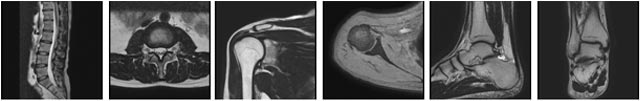

MRI検査について

当院のMRI装置はPhilips社製Ingenia1.5Tを使用しています。このMRI装置は、超電導磁気共鳴画像診断装置で人体の断面像を高画質で得ることができ、より詳細な画像を提供することで精度の高い診断が可能となります。画像を得るために使用しているエネルギーは、磁場と電磁波の為、放射線被曝はありません。しかし、金属成分を含む物を身につけて検査を行うと、非常に危険な場合があるため、問診などにより安全性の確認が重要となります。